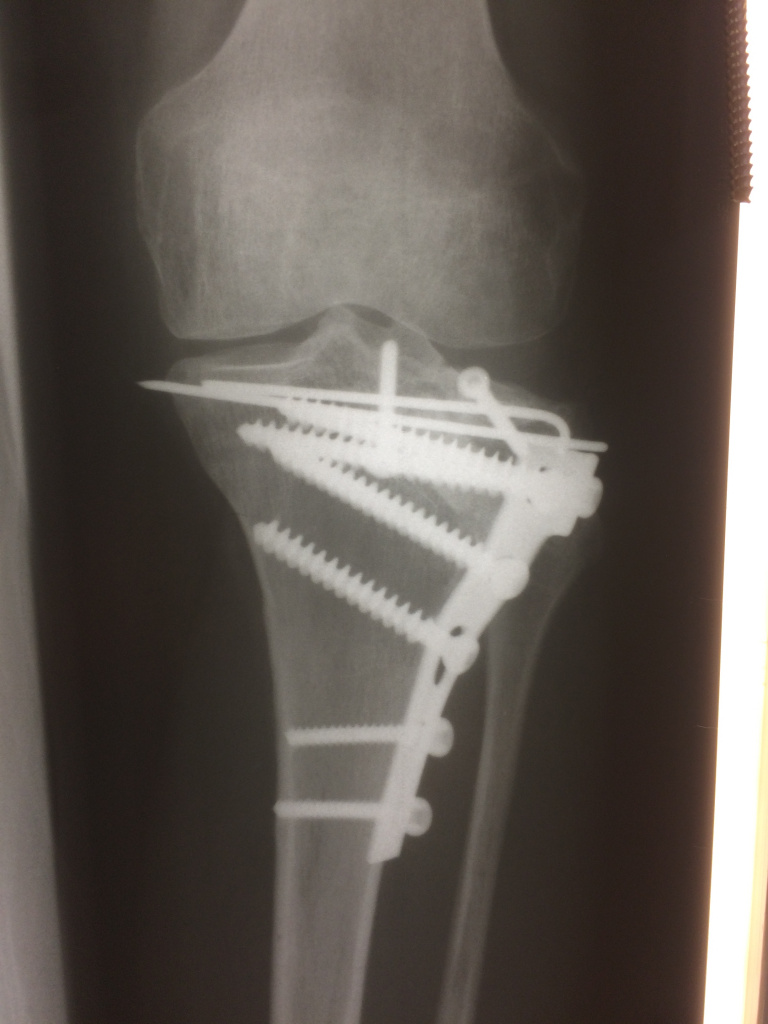

Использование материала Остеоматрикс при импрессионном оскольчатом переломе наружного мыщелка большеберцовой кости по типу Schatzker II

Использование материала Остеоматрикс при импрессионном оскольчатом переломе наружного мыщелка большеберцовой кости по типу Schatzker II.

Операция - открытая репозиция, остеосинтез большеберцовой кости опорной пластиной с костной ксенопластикой маетриалом "Остеоматрикс". На контрольных снимках в три и шесть месяцев имеется консолидация перелома, миграции фиксатора нет, имеется остеоинтеграция ксенопластического материала. Функция коленного сустава полная.